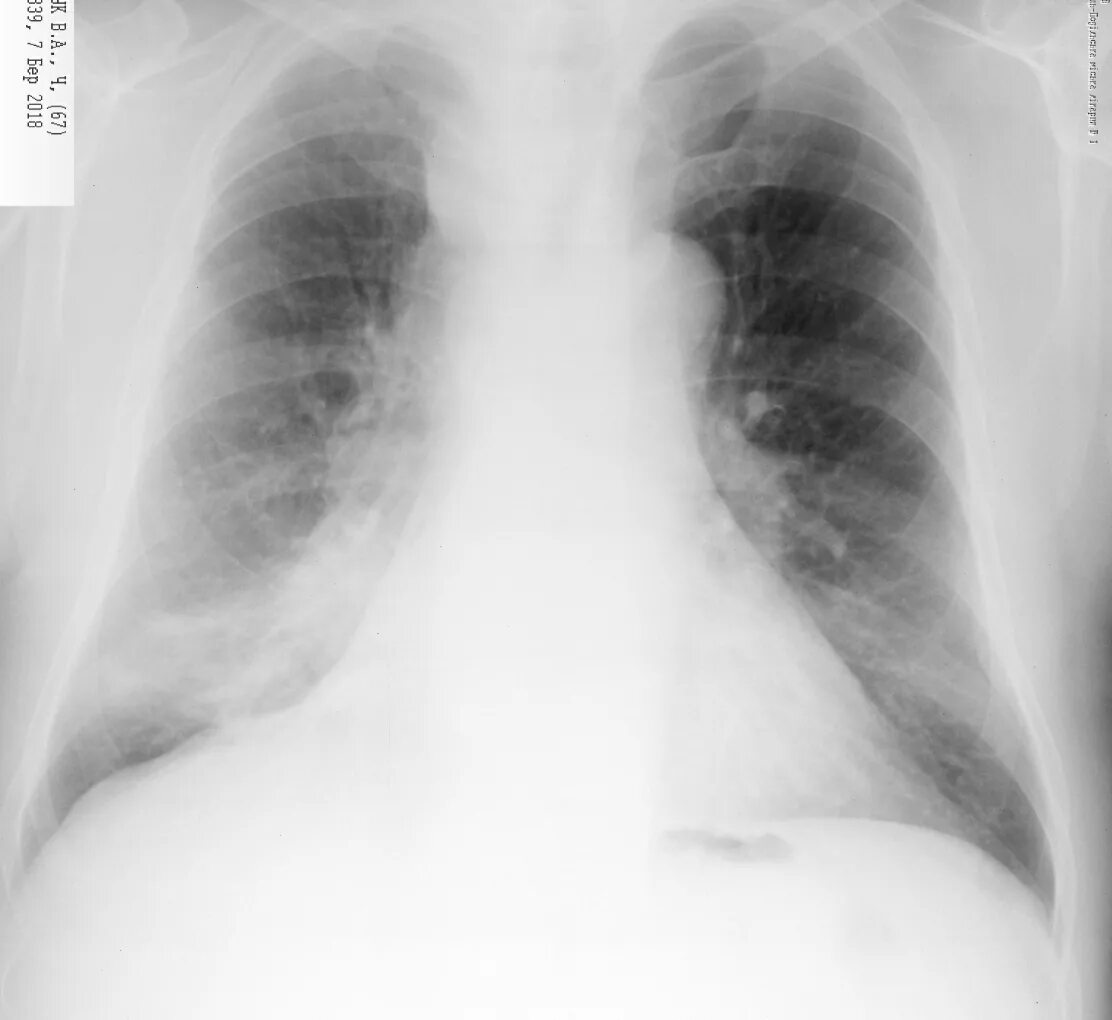

Локальный пневмосклероз легких